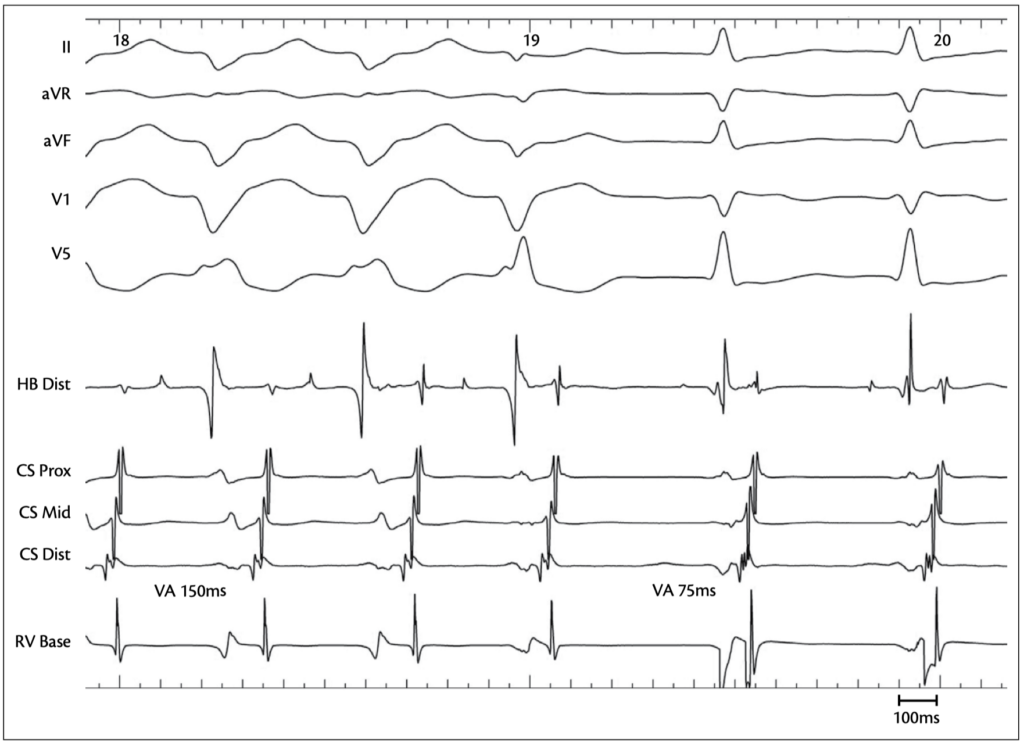

• At the level of the RV signal, activation is directed first toward

• CS 1–2 / distal, with a VA interval of 150 ms, probably due to the left bundle branch block

• The signal then rapidly returns to the His region

A ventricular premature beat shortens the AA interval, with conduction through the slow pathway, allowing the left bundle to recover, resulting in a narrow QRS.

• Recording of a ventricular signal

• Followed by rapid VA conduction of 75 ms toward CS 1–2 / distal

• With an AV interval that is prolonged due to conduction over the slow pathway